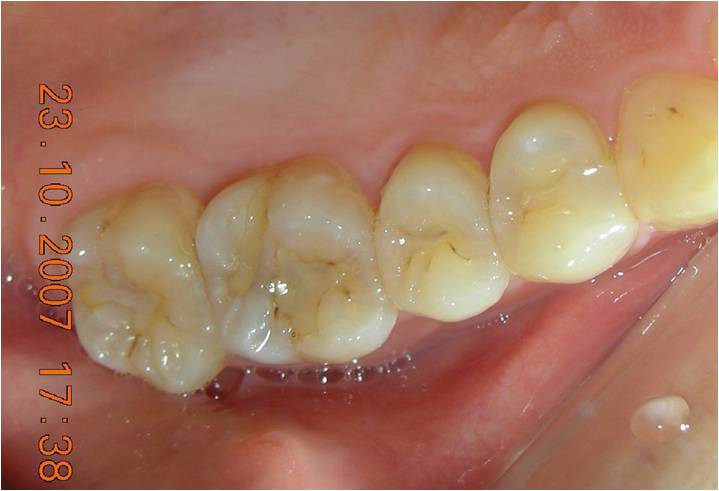

治療前,鄰接面二次蛀牙